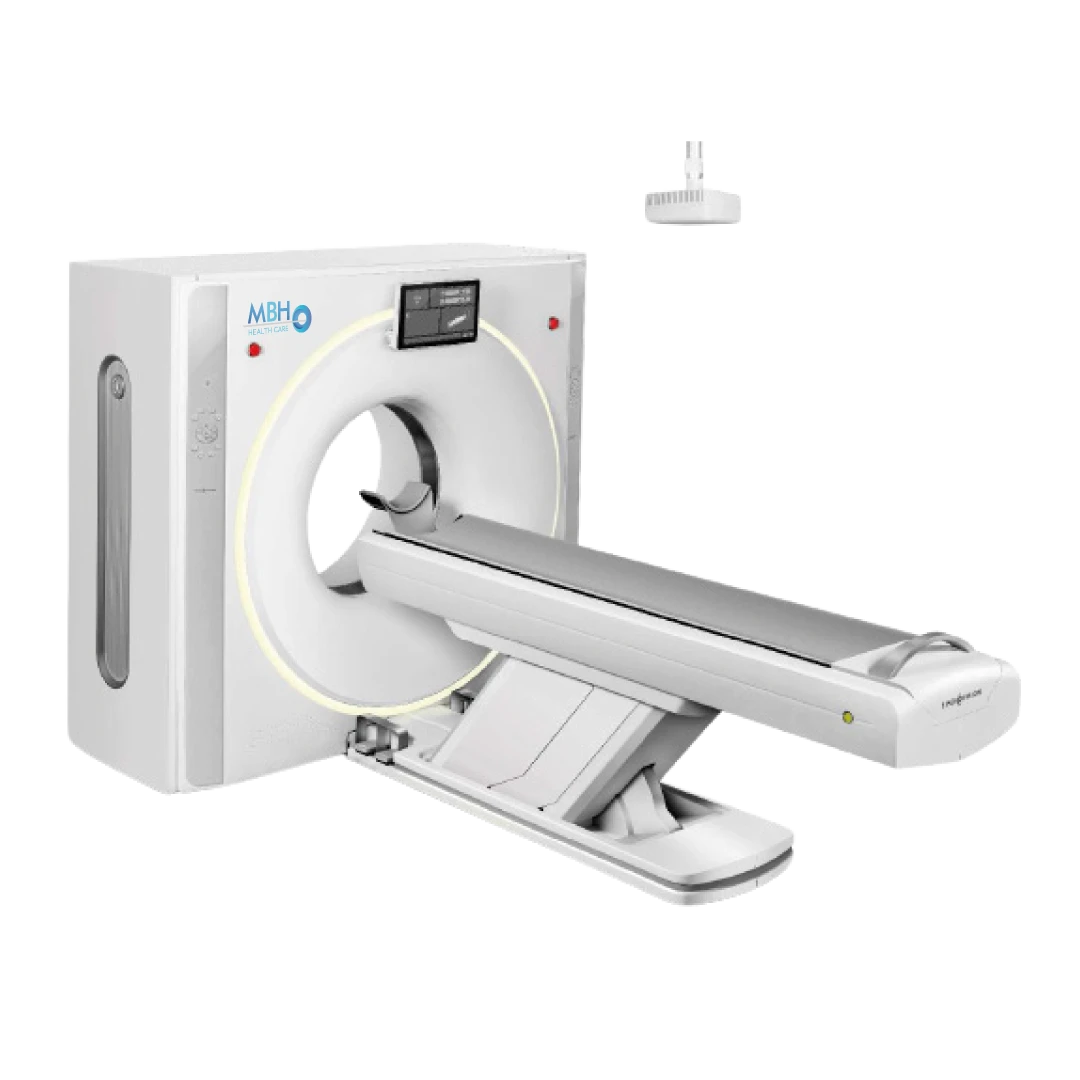

Tomograph

MBH-60

• Intelligenter 64-Zeilen-CT-Scanner mit großem Durchmesser.

- – Öffnung: 75 cm